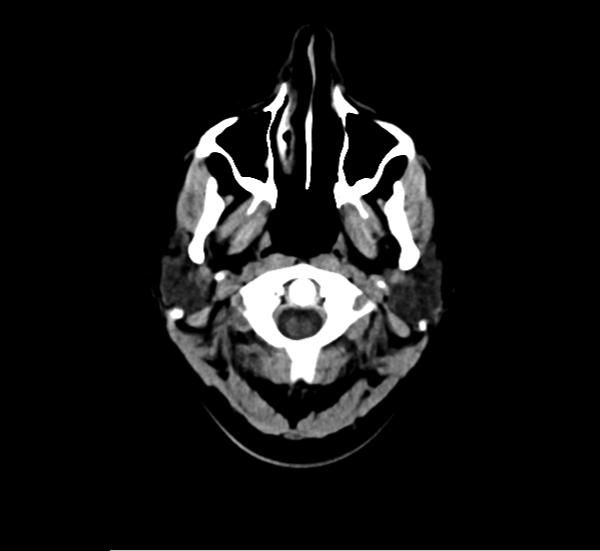

CT Brain Anatomy